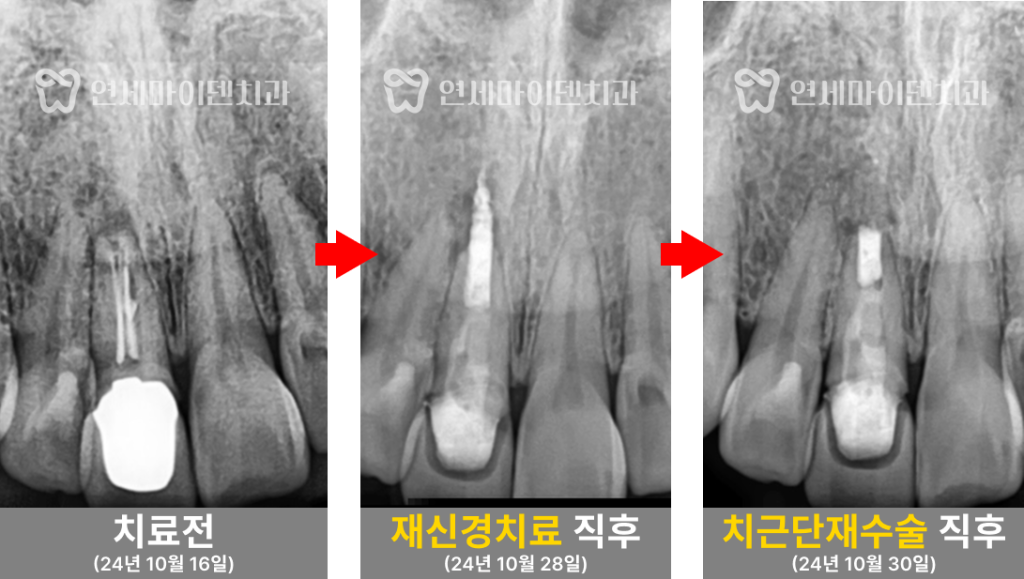

앞니 재신경치료 증례: 치근단 재수술

연세마이덴치과 닥터꼬집입니다.이번 치료 증례는 신경치료와 치근단 절제술까지 받았지만

여전히 통증이 남았던 앞니를 다시 살린 치료 과정입니다.이미 여러 단계를 거쳐 치료를 받았는데도 불편감이 지속될 경우,

이 환자분은 과거 신경치료를 받았던

앞니의 지속적인 불편감을 호소하며 내원하셨습니다.가만히 있어도 시큰거리고 불편한 증상이 있었고,

치근단 절제술까지 진행했지만

증상이 나아지지 않았던 상황이었습니다

초기 검사에서 신경치료가 제대로 이루어지지 않은 흔적이 보였습니다.

신경관 내부를 꽉 채워야 하는 신경치료 재료가 빈틈이 많아서

감염이 쉽게 발생할 수 있는 환경이었고,이는 신경치료 실패의 주요 원인 중 하나였습니다.

또한, 치근단 절제술도 진행하긴 했지만,

뿌리 끝 염증을 제거하는 과정이 충분하지 않았던 점도 확인되었습니다.📌 검진 결과 요약

3️⃣ 치근단 재수술 진행

신경치료 후에도 뿌리 끝에 남아 있는 염증 조직을 정리하기 위해

치근단 재수술을 진행했습니다.기존 절제된 뿌리 끝 부위를 다시 정리한 후,

MTA 재료로 단단히 밀봉하여 염증이 재발할 가능성을 줄였습니다.또한, 뼈 조직이 충분히 회복될 수 있도록

뼈 이식도 병행하여 치료의 안정성을 높였습니다.